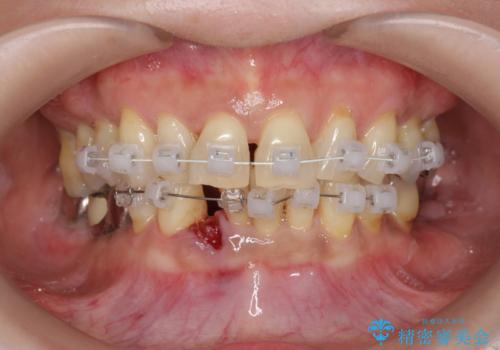

- 下顎前歯のグラつきがどんどん悪くなり、痛くて噛めなくなってきたことの改善を希望され来院されました。

下顎前歯の1本は前歯よりも前に出てしまい後ろからの力を受けることで、周囲の骨も吸収しグラつきも大きくみられます。

通常 抜歯後はインプラントやブリッジといった方法で欠損部位の機能や審美性を回復しますが、今回は臨在する歯のガタつきも利用し上下の歯を矯正治療することで人工物を装着することなく歯を並べます。